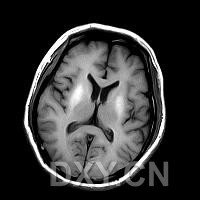

腦部病理改變與病因及病程長短有關。最重要特徵是AlzheimerⅡ型星形膠質細胞廣泛存在於大腦皮質基底核、黑質、紅核小腦齒狀核及橋核等部位程度與神經症狀嚴重程度及病程長短呈正比。慢性病例可見皮質瀰漫性片狀假分層樣壞死皮質與髓質交界處呈腔隙狀態神經細胞及髓鞘變性,部分細胞核內可見包涵體。屍檢腦部有斑片狀皮層壞死或假層狀壞死,皮質髓質連線處、紋狀體和小腦白質內有微小空腔形成。鏡下可見原漿型星形細胞數量和體積均增加。大腦皮層、小腦、齒狀核和豆狀核的神經細胞以及有髓纖維發生變性,星形膠質細胞出現含糖原的核內包含體。

2.腦部CT、MRI掃描有助鑑別診斷。